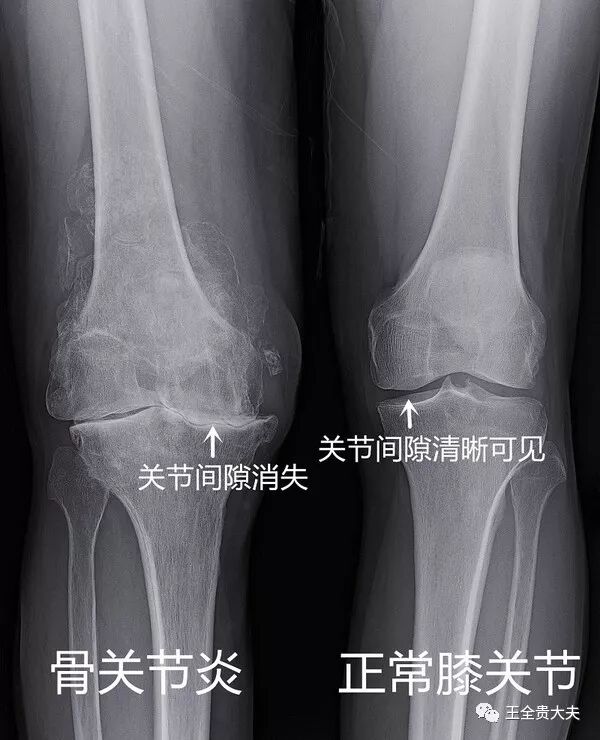

骨关节疾病问题你知道多少 王全贵大夫 微信公众号文章阅读 Wemp

膝关节炎阶梯性治疗最科学

骨性关节炎

膝骨关节骨刺的治疗方法